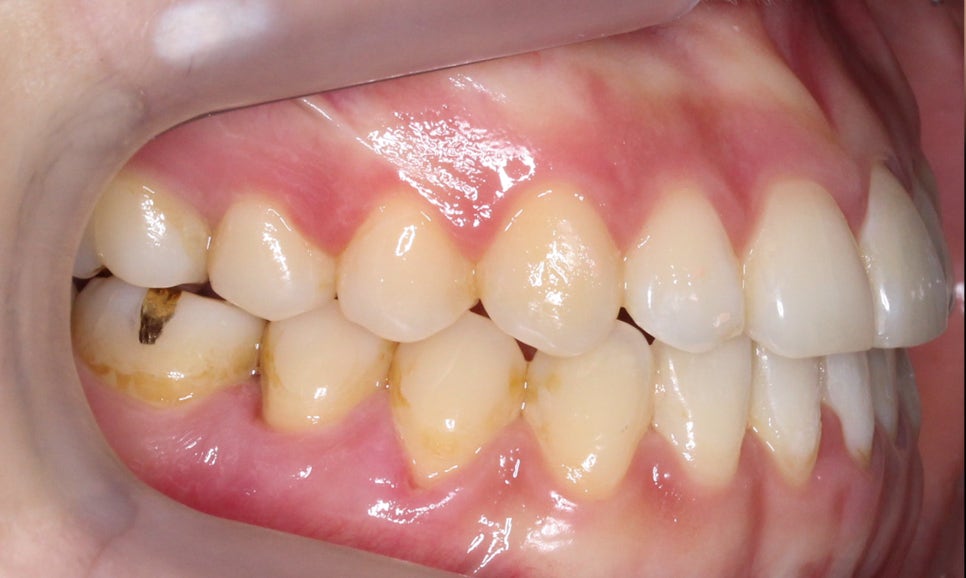

절단교합 교정 전 교합평면을 보면

상악과 하악의 교합 상태를 정확히

파악할 수 있습니다.